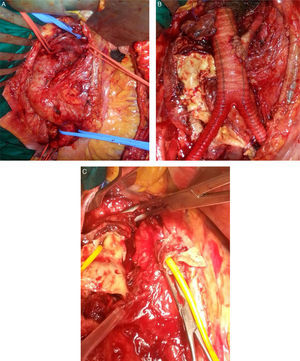

En este artículo presentamos un caso de una DA espontánea aguda de aorta abdominal infrarrenal asociada a un aneurisma de aorta abdominal, y que se intervino de forma quirúrgica en diciembre de 2013. La paciente en cuestión es una mujer de 72 años, hipertensa (HTA), dislipémica, con fibrilación auricular anticoagulada con «davigatrán», cardiopatía hipertensiva con una fracción de eyección conservada y una insuficiencia aórtica leve-moderada. La mujer acudió a urgencias por un cuadro de 9 días de evolución de dolor lumbar inespecífico, por lo que fue dada de alta con tratamiento analgésico ante la sospecha de cólico nefrítico. Debido a la persistencia del dolor, y a pesar del tratamiento, acudió al cabo de un día, de nuevo, a urgencias donde se realizó angio-TAC que objetivó una DA aguda a nivel abdominal infrarrenal con un AAA de 37mm, con falsa luz, que llega a nivel proximal a la altura del tronco celíaco sin englobar ninguna arteria visceral. Distalmente, la luz falsa progresa sin trombosis a las arterias ilíacas (fig. 1). La paciente se encontraba hemodinámicamente estable, y a la exploración física presentaba pulsos distales y exploración abdominal anodina. Ante los hallazgos radiológicos se decidió realizar cirugía abierta urgente mediante bypass aorto-bifemoral con clampaje suprarrenal y reimplante de la arteria renal izquierda, previa instilación de suero Ringer frío en ambos riñones. En la intervención se fijó la capa íntima en todas las anastomosis (fig. 2A-C).